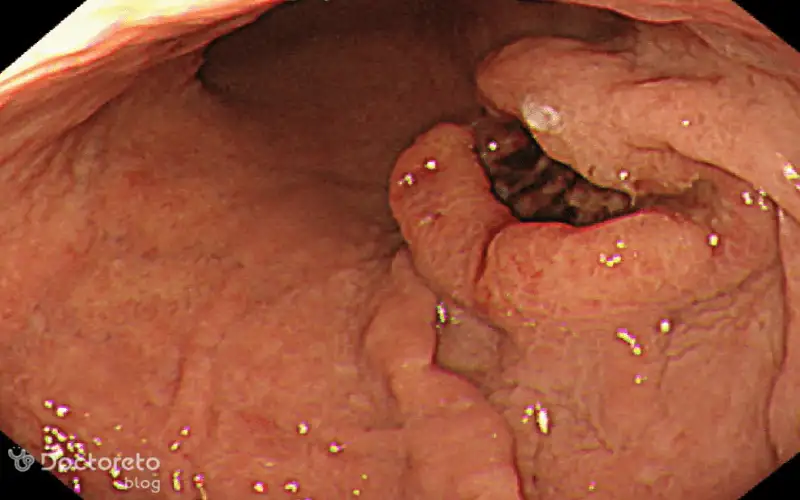

عکس زخم سرطان معده بدخیم

زخمهای ناشی از سرطان معده ممکن است در ابتدا شبیه به زخم معده معمولی باشند، اما با گذشت زمان شکل، اندازه یا حالت آنها تغییر میکند. حتی ممکن است علامت پیشرفتهتری از بیماری باشند. این نکته اهمیت تشخیص درست و سریع را بیشتر میکند. در ادامه تصویری از زخم ناشی از سرطان معده بدخیم را مشاهده میکنید.

عکس آندوسکوپی سرطان معده بدخیم

آندوسکوپی یکی از روشهای مهم تشخیصی برای سرطان معده بدخیم است که در آن از یک لوله نازک با دوربین برای مشاهده داخل معده استفاده میشود. این روش امکان نمونهبرداری (بیوپسی) و مشاهده مستقیم تومور را فراهم میکند. این تکنیک در تشخیص زودرس بیماری نقشی مهم دارد.